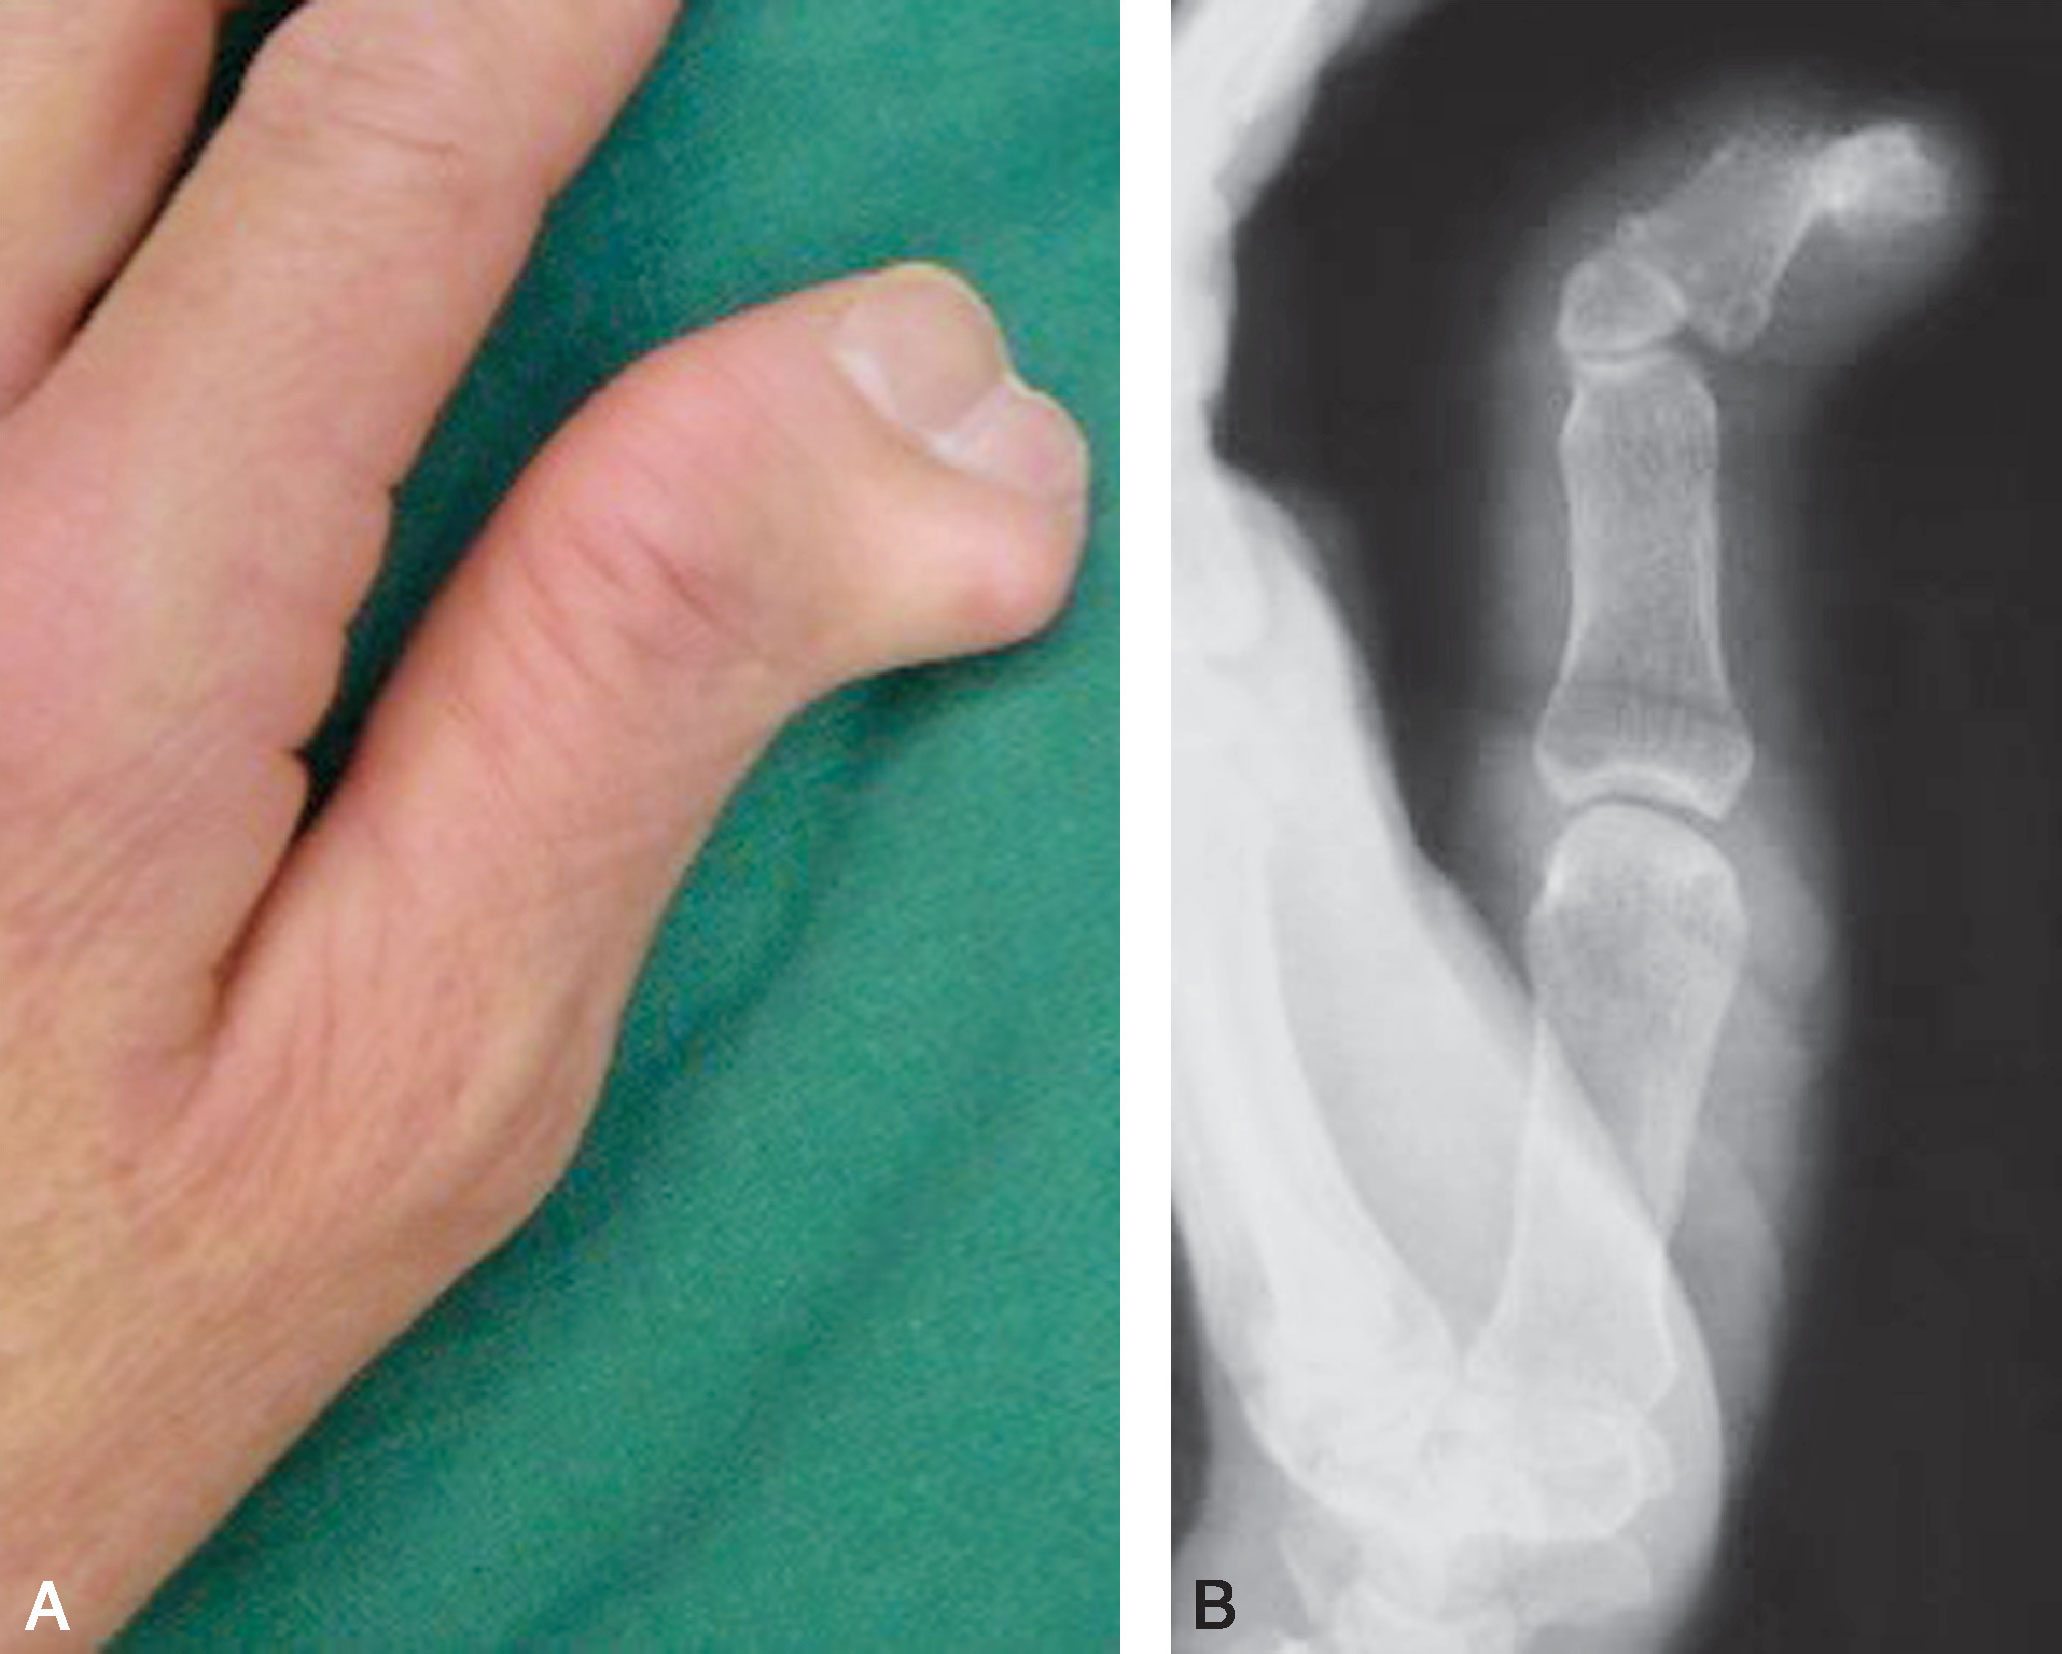

图2-1-3 Ⅰ型病例3

A.体位像显示主、次拇指指甲完全融合在一起,似一个指甲,应选择切除桡侧赘拇,然后需重建甲沟,并尽可能与对侧对称;B.X 线片显示,远节指骨分叉,桡侧部分细小,切除容易,但切除后应注意保持主拇指基底桡侧骨骺板开放。 由于远节指骨基底骨骺为不正常的倒V 形,术后骨骺生长仍可能异常,导致保留下来的远节指骨偏斜,需进一步截骨矫正

图2-1-4 Ⅰ型病例4

A.“镜影拇指”,主、次拇指外形及大小几乎一致;B.X 线片显示主、次拇指远节指骨几乎等大,是主、次拇指融合的适应证。 也可切除桡侧拇指,保留尺侧拇指,同时行保留的尺侧远节指骨基底骨骺端的桡侧闭合楔形截骨,但需保护骨骺板